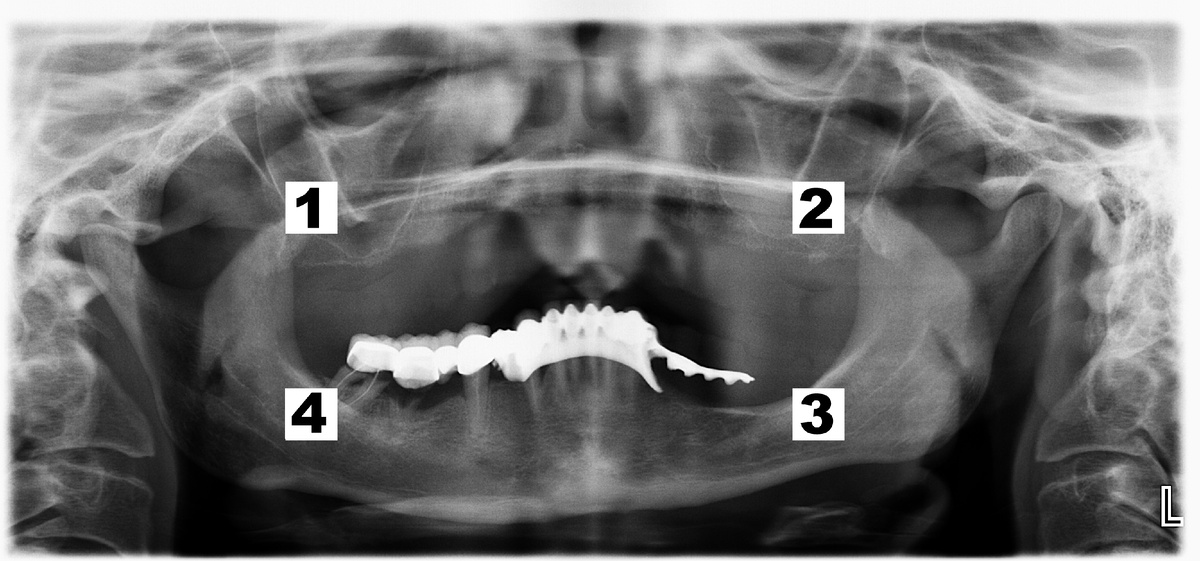

Справа (сегмент 4 на снимке ОПТГ ☝️) — протяженный мостовидный протез из металлокерамики с опорой на собственные зубы 4.8 (зуб мудрости) и 4.4

- Зуб 4.8 и 4.5 пролечены не до конца, кариес корня, разъединение полностью под коронкой

- Корень зуба 4.7 практически полностью растворился

- Глубокие пародонтальные карманы между зубами 4.5 и 4.3, а также между 4.3 и 4.2

- Передние резцы, служившие опорой бюгельному протезу и коронкам из металлокерамики, несостоятельны

Слева (сегмент 3 на снимке ОПТГ ☝️) — хитрый бюгельный протез с металлическим основанием, фиксацией за клыки 4.3 и 3.3? замещающий зуб 4.4 и протяженностью 4 единицы

На снимке ОПТГ протез выглядит 👀 как хвостик, висящий в воздухе

От верхнего уровня альвеолярного гребня до тройничного нижнечелюстного нерва всего 8 мм. Это проблема, т.к. в данной области нерв не позволит установить имплантаты длиннее 6 мм, причём даже при установке таких коротких имплантатов риск получить в итоге парастезию (онемение) чрезвычайно высок.